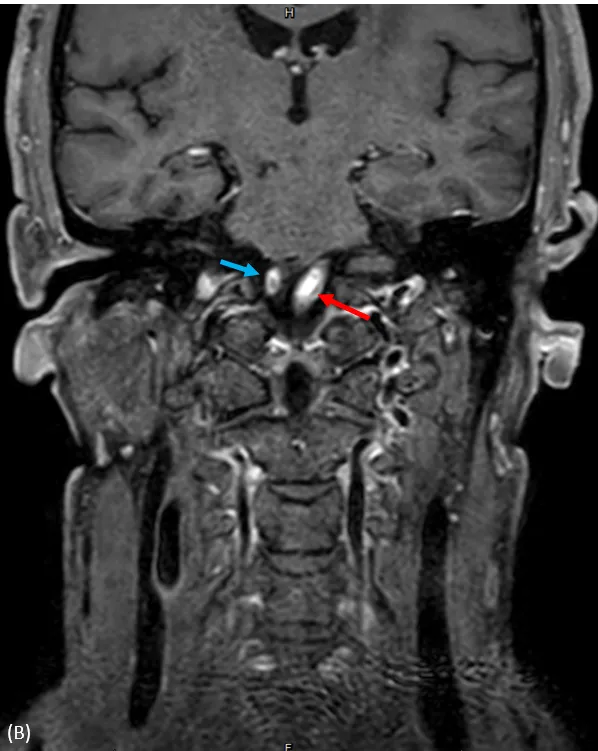

核磁共振血管攝影,顱內左(紅色箭頭)及右(藍色箭頭)椎動脈高度狹窄或是完全阻塞。大里仁愛醫院提供